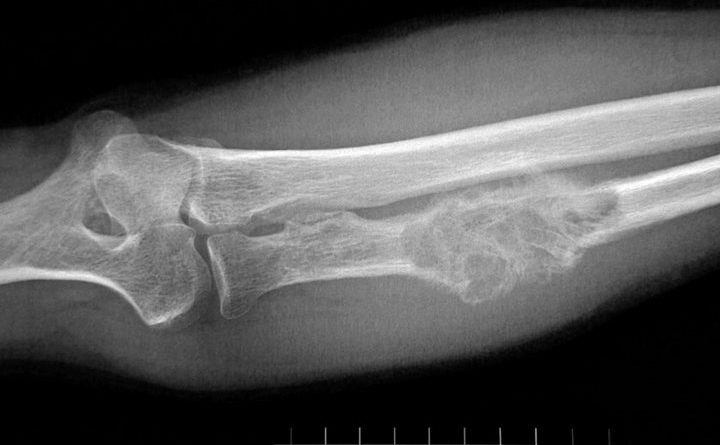

Bone cancer is a primary or secondary form of cancer. Primary bone cancer is where it begins in the bone. From there, the cancer will then begin to develop in the cells of the bones. Secondary bone cancer is where it begins in other areas of the body.

Once this has occurred, the cancer will then start to spread to the bones. When a tumor in the bone develops, it will press on the healthy tissues of the bones. As a result, these tissues may be destroyed. In this article, we will have a look at what the symptoms and signs of bone cancer are.

Swelling and pain are likely to be what you will experience in the early days of bone cancer. Particularly where the tumor is sitting. There will be times where the pain will come and go. However, it will eventually become more steady and severe as the cancer progresses. The pain may also become worse when you move around. Soft tissue swelling near the pain may also occur.

If you have a tumor located in or around joints, then the joint may begin to swell. This swelling may become stiff or tender. If this happens, a person who experiences this may not be able to move around much without some form of pain.

Other signs and symptoms of bone cancer may include: tingling, weakness or numbness of the bones. Particularly if the cancer is in the spine area. Fatigue and weight loss might also occur. Difficulty breathing may also be experienced if the cancer reaches the lungs. A weakening of the bones. Less common signs and symptoms individuals may experience may include: a low level of red blood cell, anemia, arthritis, fevers, chills, sweating at night.